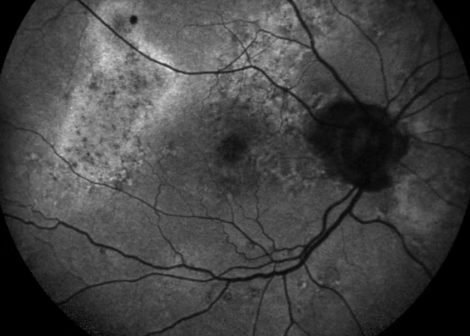

At their first meeting, Ms Heng reviewed all previous scans, ordered high-resolution imaging, and confirmed an aggressive form of central serous chorioretinopathy (CSCR). She explained the condition in plain language, outlining how fluid beneath the macula distorts central vision and, in chronic cases, scars the retina. “CSCR resolves in most people, but in a minority it becomes chronic and can rob them of their sight. Robin’s presentation was very complex, so we carried out a comprehensive evaluation and devised an evidence‑based treatment plan to optimise his outcome, and I am incredibly happy with the success of his treatment,” said Ms Heng. Photodynamic therapy (PDT) was selected as the first step because it typically seals leaking vessels without the need for surgery.

Follow‑up imaging showed that PDT had not halted fluid leakage. Robin was developing very quickly with new foci of fluid every 4 weeks and losing vision in his good eye. He developed very rare form of choroidal neovascularisation in both macular secondary to CSR. Refusing to let Robin's progress stall further evaluation was performed including full blood profile and MRI of the head looking for possible other rare causes which yielded negative results. Robin was started on eylea 2mg the treatment for new vessels, however, this produced suboptimal results. He was progressing much faster than the effect of the treatment. Ms Heng then analysed further emerging evidence, spoke to multiple colleagues and the manufacturer representative for eylea 8mg to look at evidence of utilising this newer antivegf agent on the market for anecdotal evidence for treatment response. Given the rapid progression of disease, and analysing the patient’s progress and response to the earlier treatment, Ms Heng carefully described the benefits and potential risks clearly, enabling an informed choice to start the patient on a course of antivegf Eylea 8mg.

CSCR affects the macula, the part of the retina responsible for sharp central vision. While most cases resolve within six months, chronic or aggressive variants like Robin's can scar the retina and lead to permanent sight loss. Robin's outcome underlines the importance of early referral to sub‑specialists and flexible, personalised management when standard approaches prove insufficient.